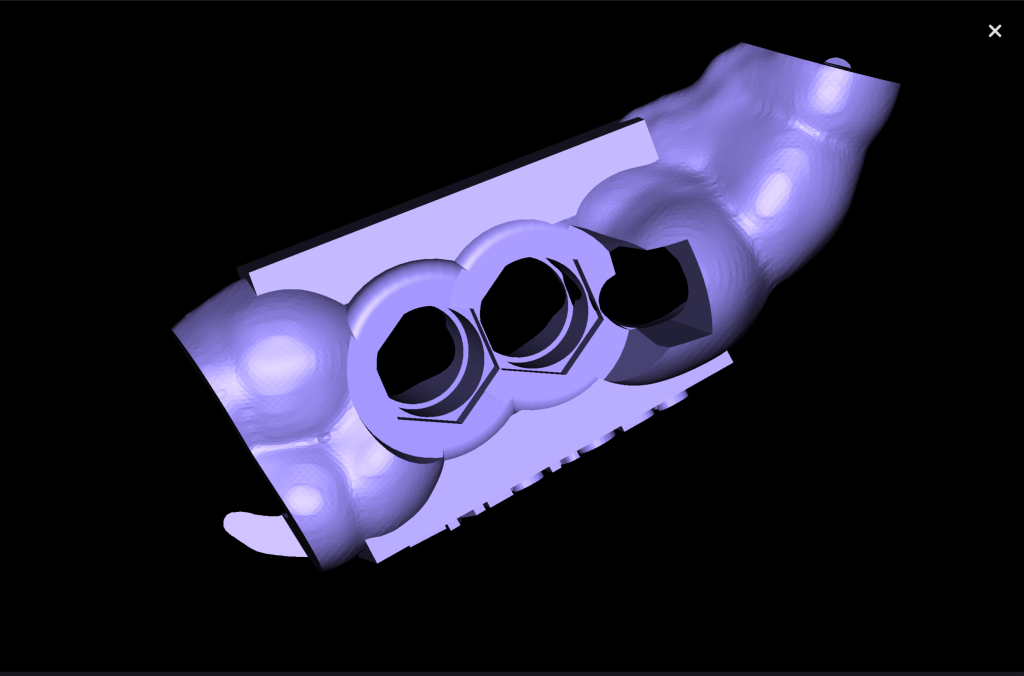

A template for guided implant surgery was planned and manufactured based on these digital models for the replacement of teeth 24 (Universal 12) and 25 (Universal 13)

Based on digital models, a virtual design of a template has been planned for the replacement of tooth 36 (Universal 19)